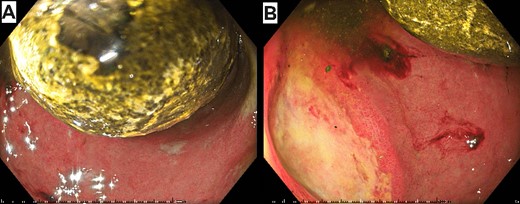

A nasogastric tube successfully decompressed the stomach before the patient was taken for gastroscopy. There, the impacted gallstone was visualized between the first and second parts of the duodenum (Fig. 2). Multiple attempts to extract the gallstone with various instruments were unsuccessful and the procedure was abandoned. Laparoscopic gastrotomy and stone retrieval was planned for 3 days’ time. The patient was kept fasted with total parenteral nutrition and intravenous piperacillin–tazobactam in between the cases. During the operation there was difficulty mobilizing omentum that was adherent to the fistula. An intraoperative gastroscopy was able to enter the cholecystoduodenal fistula as well as the third part of the duodenum, failing to reveal the impacted gallstone. A cholecystotomy displayed a gallbladder clear of stones. The small bowel was inspected and the gallstone was encountered ~30 cm distal to the duodenojejunal flexure. Here, it was again obstructing with proximal small bowel distension. Laparoscopic enterolithotomy was successful in retrieving the stone (Fig. 3). The cholecystotomy was sutured close. The patient was discharged eight days later following an unremarkable post-operative recovery. At 4- and 6-week follow-up, the patient was well and remained pain free with no new issues.

Initial gastroscopy showing impacted gallstone between the first and second parts of the duodenum (A) and the cholecystoduodenal fistula (B).